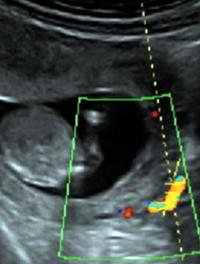

L’arrivée sur le marché français en août 2013 de l’acétate d’ulipristal, un modulateur sélectif de la progestérone (SPRM), indiqué dans le traitement du fibrome, a permis de réduire sensiblement le nombre d’interventions chirurgicales pour ce motif.